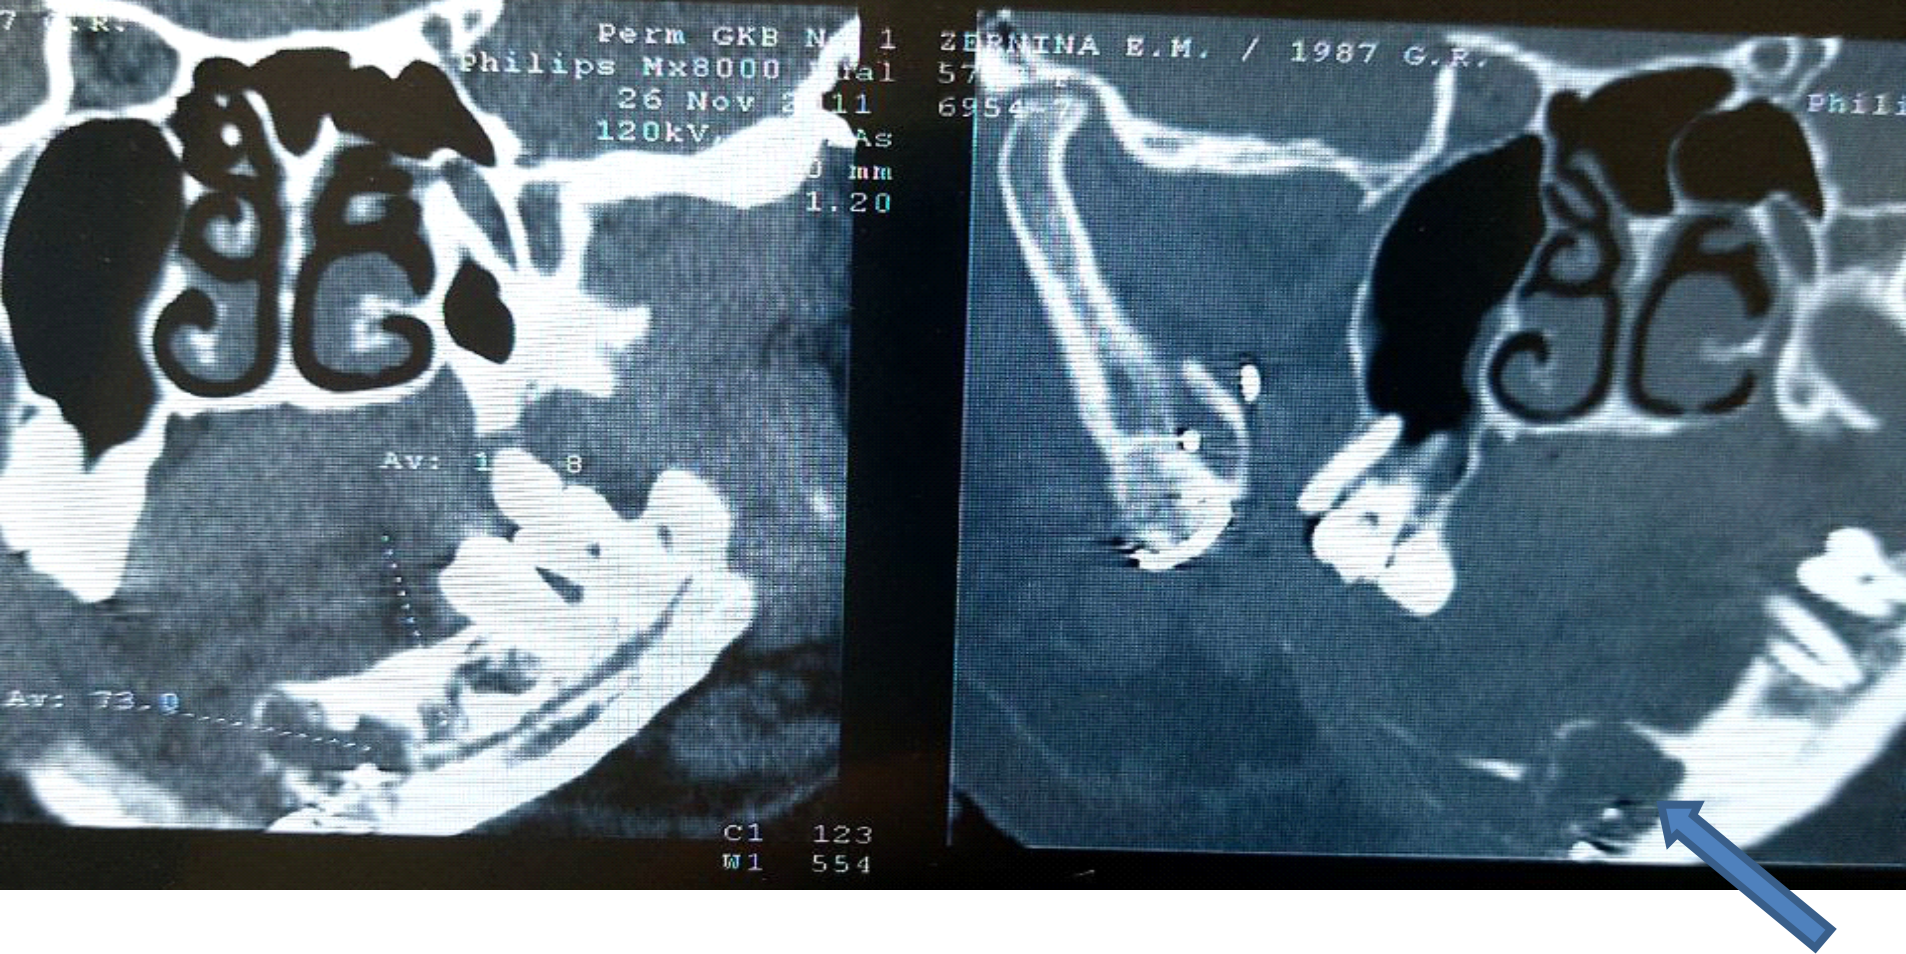

A CT scan of the upper jaw was performed. In the area of the frontal part of the upper jaw on the left, a neoplasm of a non-uniform structure, cellular in shape in the projection of teeth 1.3–1.1, with a cuff-shaped thickening of the alveolar part was found (Fig. 4).

Fig. 4. CBCT: tumor in the upper jaw area, 2011

After receiving the results of an incisional biopsy, a diagnosis of osteoclastoma of the frontal maxilla was established (ICD 10 code – D16.4). A resection dentofacial prosthesis for the upper jaw was made according to the defined boundaries of the partial resection of the upper jaw. Surgical treatment was performed – removal of a neoplasm in the area of the frontal part of the upper jaw on the left with partial resection of the upper jaw, with closure of the surgical wound with a flap from the mucous membrane of the cheek and one-stage replacement of the defect with a resection prosthesis. In the postoperative period, a course of anti-inflammatory therapy was administered. As a result of additional examination, a control CBCT scan revealed a neoplasm in the frontal part of the lower jaw on the right side from the lingual side. An incisional biopsy was performed. The diagnosis was established: D16.5 – osteoclastoma of the lower jaw on the right, relapse (Fig. 5), confirmed by the results of pathohistological examination.